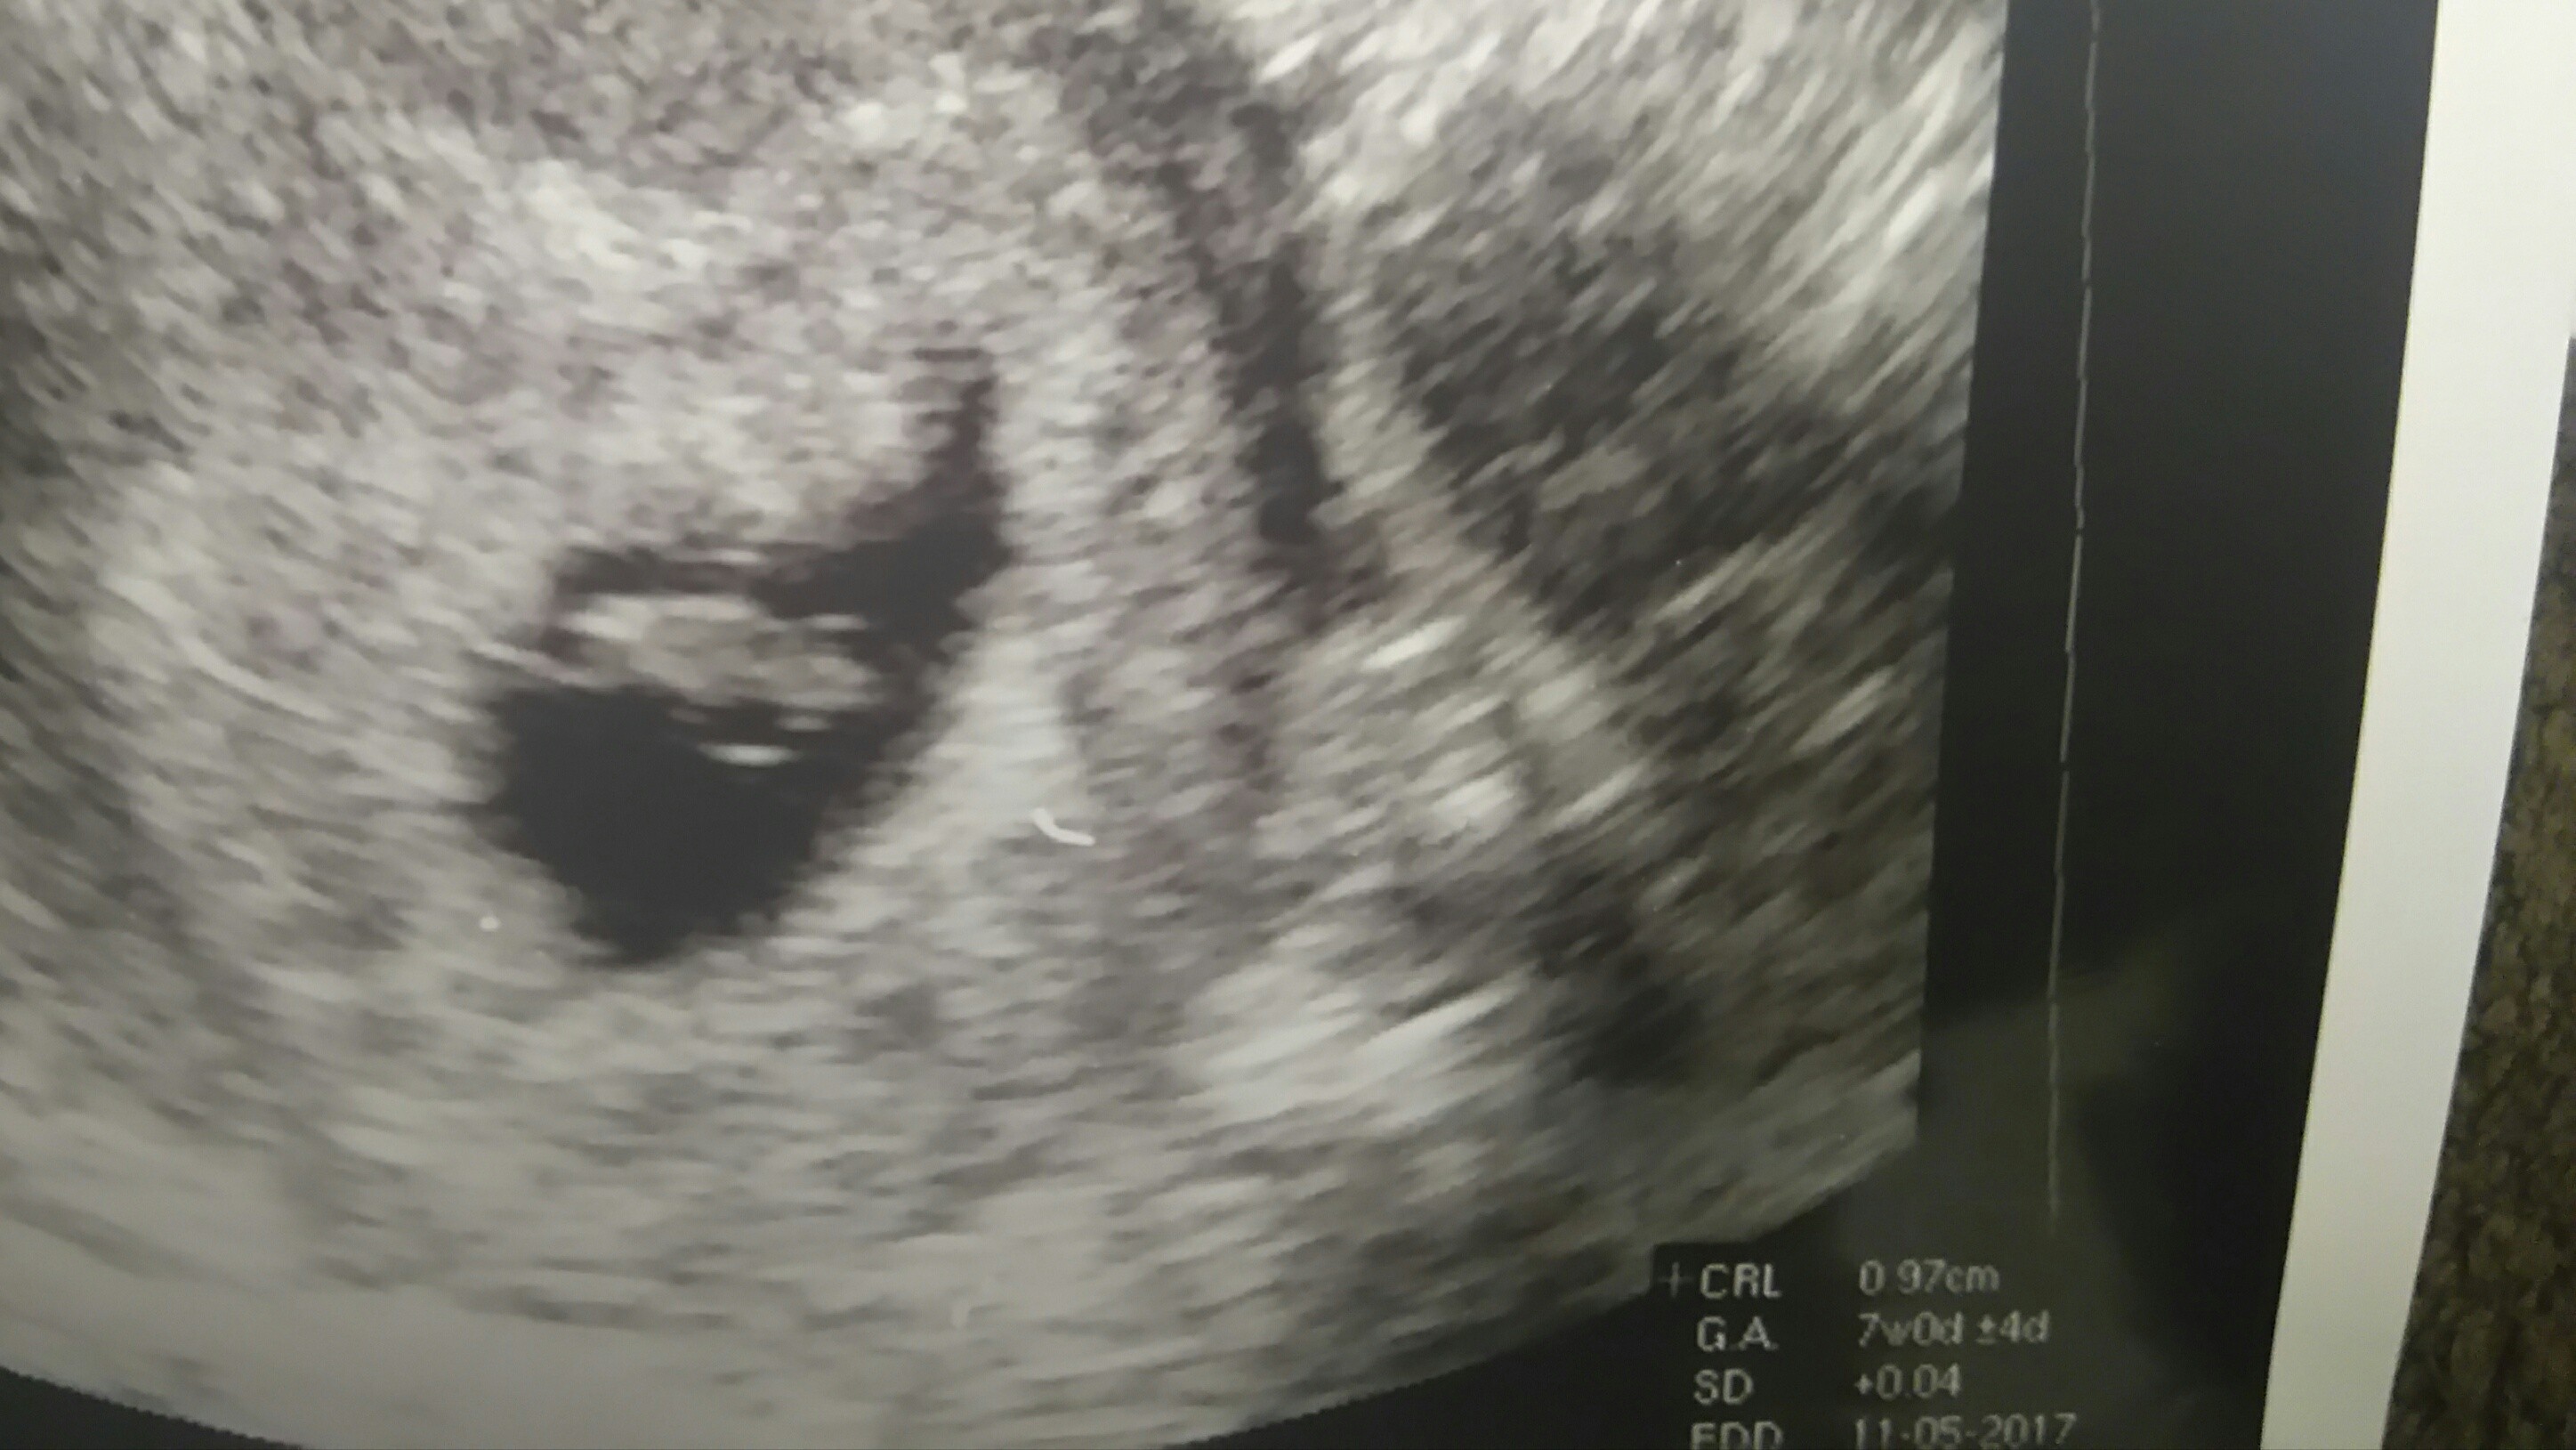

Ja już po pierwszej wizycie... Mega szczęśliwa... Z OM 6t5d... Z usg 7t0d... Serduszko ❤ biło... wszystko w porządku... Moje szczęście ma 0,97cm.